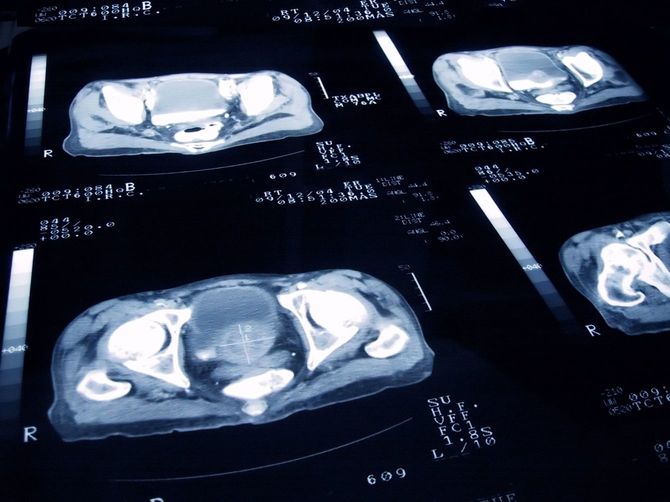

MRIの結果は、前立腺がんステージ4だった

2021年5月。腰、肩、肩甲骨の痛みがひどいため、山田さんは3カ月ほど寝込んでしまう。ようやく整形外科を受診し、MRIを受けたところ、すぐに総合病院への紹介状を用意された。2日後、検査結果を聞きに行くと、前立腺がんのステージ4であることが告げられた。母親が息子を息子とわからなくなるショッキングな出来事から半年、さらなる衝撃に直面したことになる。